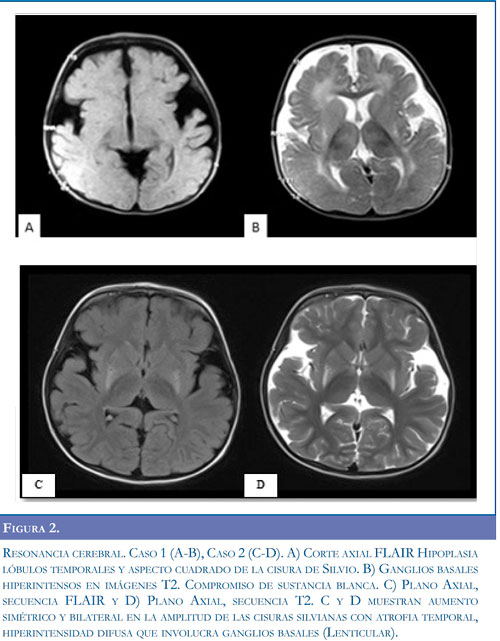

Neuroinfección, la cual se descartó por análisis de líquido cefalorraquídeo, se inició manejo anticonvulsivante con fenitoína y fenobarbital ante la sospecha de crisis epiléptica; sin obtener mejoría. Presentó síntomas respiratorios, con radiografía de tórax que mostró opacidad alveolar derecha y hemograma con aumento de leucocitos a expensas de neutrófilos, por lo cual se inició tratamiento antibiótico. Se remitió a Hospital de III nivel para manejo especializado. Al examen neurológico se encontró alerta, irritable, con sialorrea, nistagmus horizontal, hipertonía generalizada, hiperextensión de extremidades y cabeza, hiperreflexia con clonus aquiliano bilateral, respuesta plantar extensora bilateral, movimientos distónicos, y pérdida de las habilidades motoras previamente alcanzadas. Se realizó electroencefalograma sin evidencia de actividad paroxística epileptiforme, y se suspendieron los anticonvulsivantes. Las imágenes de tomografía axial computadorizada de cráneo (TC) evidenciaron atrofia bilateral de lóbulo temporal (Figura 1A). Con impresión diagnóstica de encefalopatía con disquinesia de probable origen metabólico se inició manejo con diazepam para control de crisis distónicas. Se realizó resonancia magnética (RM) cerebral evidenciando hipoplasia fronto-temporal, con aumento del tamaño de las cisuras silvianas, retardo en la mielinización y alteración de la señal en ganglios basales (Figura 2).

Caso 2. Femenina 3 años de edad, hermana del paciente anterior, con antecedente de retardo global del desarrollo, sin que hubiera adquirido marcha independiente. Al examen físico, estaba alerta, con pobre relación con el medio, sialorrea persistente, lenguaje con monosílabos, aumento del tono en las 4 extremidades, hiperreflexia generalizada, marchaba con apoyo en puntas de pies, incoordinación motora y posturas distónicas asociadas. Las imágenes de TC reportaron atrofia temporal bilateral, con amplitud de la cisura de Silvio (Figura 1 B). Las imágenes de resonancia magnética cerebral mostraron hipoplasia fronto-temporal con aumento de la cisura silviana y compromiso ganglio basal (Figuras 2 C-D). La determinación de ácidos orgánicos de cadena corta y media confirmó el diagnóstico de aciduria glutárica tipo I (Tabla 1). Se inició manejo nutricional con restricción proteica libre de lisina y baja en triptófano, suplementación con L-carnitina y benzodiacepina para el manejo de las distonías. Cuatro meses después continúa manejo nutricional y farmacológico, controles ambulatorios y terapia integral, evidenciando mejor relación con el entorno, mejoría en lenguaje expresivo y asistencia al jardín infantil.

La sospecha clínica fue apoyada en todos los pacientes con imágenes típicas de atrofia frontotem-poral bilateral conocidas como "alas de murciélago" en la tomografía axial computadorizada y por alteraciones de la sustancia blanca en grados variables en la resonancia magnética cerebral como se describe en la literatura (11).